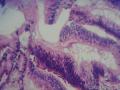

直肠肿物

性别年龄60岁临床诊断

一般病史血便一个月。

大体所见破碎的灰白组织V:0.5X0.4X0.3CM。

管状-绒毛状腺瘤

绒毛—管状腺瘤伴低级别上皮内瘤变

绒毛-管状腺瘤伴低级别上皮内瘤变。